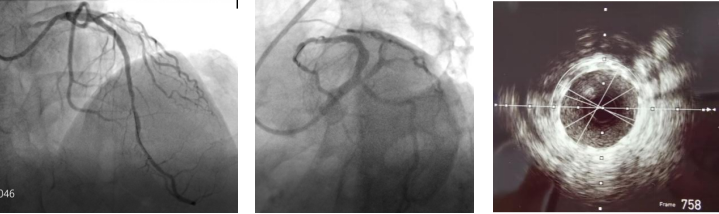

在楚天舒主任指导下,团队顺利使用Shockwave IVL震波球囊对钙化病变处进行多个周期的冲击波治疗。治疗中可见冲击波球囊逐渐扩张开顽固钙化区域,冲击波治疗后复查造影可见左前降支近中段的钙化狭窄处明显改善。术中植入的2枚药物洗脱支架在行IVUS中可见支架贴壁和膨胀良好,血管扩张成形满意。术中患者无明显不适,未见低血压、ST改变及心律失常,术后患者胸痛症状明显好转。目前,该患者病情平稳,胸痛症状完全缓解。

术后造影